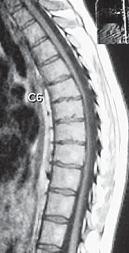

МРТ № 52

Иллюстрация к книге — Остеохондроз для профессионального пациента [i_083.jpg]

На МРТ № 51 наблюдается грудной отдел позвоночника с нормально выраженным физиологическим кифозом, межпозвонковыми дисками и спинным мозгом.

На МРТ № 52 наблюдается усиление грудного кифоза (гиперкифоз), снижение высоты межпозвонковых дисков с деформацией замыкательных пластин, расширением тел позвонков в вершине кифоза и самое главное — перерастяжение и уплощение спинного мозга на уровне вершины искривления.

Рассмотрим вариант нормы и патологии грудного отдела позвоночника (МРТ № 51, МРТ № 52). Конечно, заболеваний, которые могут проявиться вследствие развития остеохондроза грудного отдела позвоночника, достаточно. В каждом отдельном случае необходимо установить точный диагноз, осуществить грамотный подход в выборе методов лечения. Нельзя недооценивать возможные вариации развития заболевания. Вот, например, из-за таких деформаций позвоночника, которые можно наблюдать на МРТ № 52, порой возникают парезы или параличи, зачастую вследствие развивающегося ишемического «миелита», точнее спондилогенной миелопатии — перерождение вещества спинного мозга из-за недостаточного кровоснабжения. Причём то же клиническое течение спондилогенной миелопатии может протекать двояко. Чаще заболевание развивается исподволь, постепенно в течение довольно длительного времени. Порой останавливается, так и не достигнув своего апогея. А бывает (хотя и намного реже) в течение относительно короткого отрезка времени, на фоне полноценной функции спинного мозга, возникают парезы и параличи. Что лежит в основе этого тяжелейшего осложнения — спондилогенной миелопатии? Как правило, расстройство кровоснабжения спинного мозга. Оно, в свою очередь, возникает вследствие нарушения проходимости питающих его артериальных кровеносных сосудов. Опасность здесь таится в том, что значительный по длине спинной мозг, занимающий почти всю протяжённость позвоночника, получает кровоснабжение всего из нескольких артерий. Если даже одна из таких питающих артерий вследствие перерастяжения или сдавления «закупоривается», то значительные территории спинного мозга лишаются кислорода, питательных и других веществ, что приносит с собой его тканям артериальная кровь. Нарушение проходимости питающих спинной мозг кровеносных сосудов возникает вследствие их перерастяжения вместе со спинным мозгом и его элементами, что или приводит к сужению просвета растянутого артериального ствола или к прямому сдавлению его деформированными костными структурами позвоночника. Нервная ткань спинного мозга очень чуткая к недостаточности кровоснабжения и быстро гибнет в условиях неполноценного притока артериальной крови. Это, в свою очередь, приводит к возникновению частичных и полных параличей тех органов, которые зависят от поражённых территорий спинного мозга. Вот такая выстраивается цепочка, где одно событие неумолимо порождает другое и приводит к определённым последствиям.